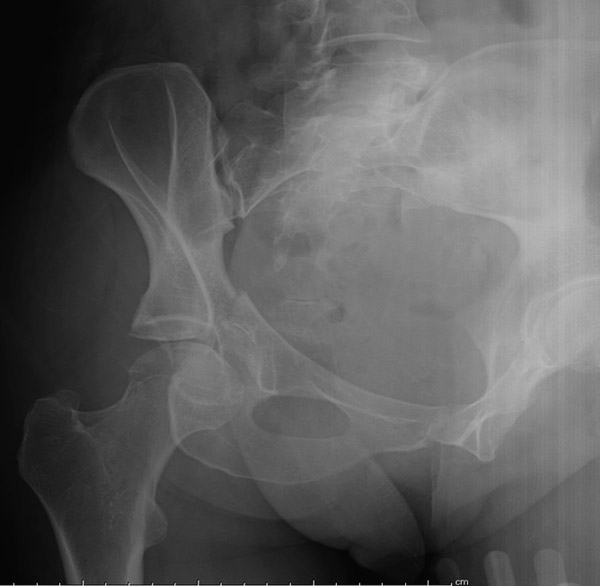

Перелом вертлужной впадины отличается от “переломов таза” не только исследованием, но также тактикой. По классификации Летурнеля расположение линии перелома характерно для поперечного перелома вертлужной впадины, но наличие шурупов в заднем крае (второй снимок) и вывих бедра подтверждают, что здесь сочетание заднего края с поперечным переломом.

Через задний доступ смогли сделать частичную репозицию, а здесь напрашивался двойной доступ спереди и сзади. Репозиция в положении на боку затруднительна, и вытяжение за перекладину над операционным столом облегчило бы репозицию.

Здесь пара случаев, где обычный поперечный перелом зафиксирован задним доступом и второй поперечный перелом в сочетании задней стенки, где на КТ слева в шейке обнаружен перелом без смещения, который зафиксирован профилактически.